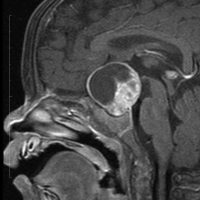

7歳の子が視力障害で発症しました。両耳側半盲という症状です。典型的な鞍隔膜下頭蓋咽頭腫です。ガドリニウム造影剤を入れないMRIでみえる,黄色い矢印の先の白い高信号は抗利尿ホルモンです。ですから下垂体機能もまだ残っていて,尿崩症はありません。視力障害が戻らないことがあるのでなるべく早く,経鼻的な手術で摘出した方がいいものです,簡単 o(^-^)o